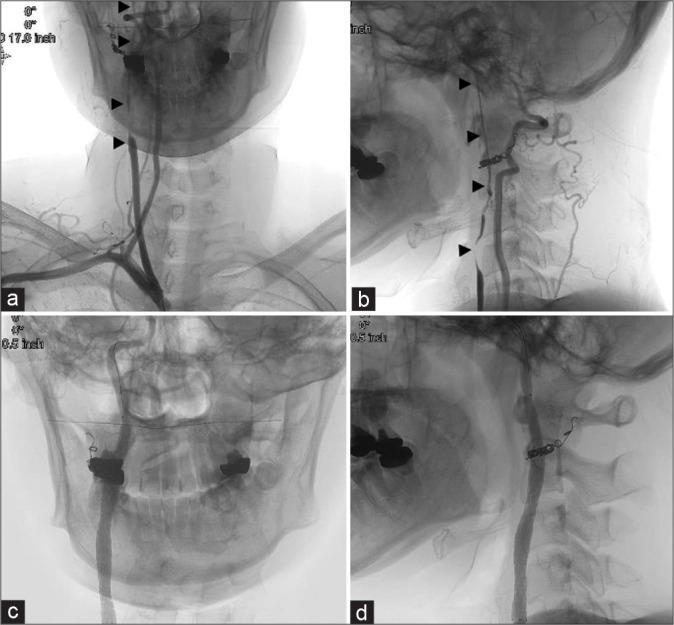

A woman in her 20s experienced injury to the right carotid artery during an operation for removal of a carotid body tumor 6 years before presentation. The right common carotid artery and internal carotid artery were replaced with an artificial vessel graft at that time. Intraluminal stenosis in the graft was not identified 3 years after surgery; however, 4 years after surgery, stenosis was recognized at the non-anastomotic site inside the artificial vessel graft. Subsequently, antiplatelet therapy was initiated. The stenosis was noted to progress gradually in follow-up appointments. Therefore, we decided to intervene because of the patient's young age and the risk of long-term hemodynamic stress. Angiography revealed pseudo-occlusion in the artificial vessel. Percutaneous transluminal angioplasty was performed for stenosis with distal protection; subsequently, CAS was performed. The patient was discharged without neurological deficits 4 days after the operation, and no apparent restenosis was observed as of the 1-year follow-up.